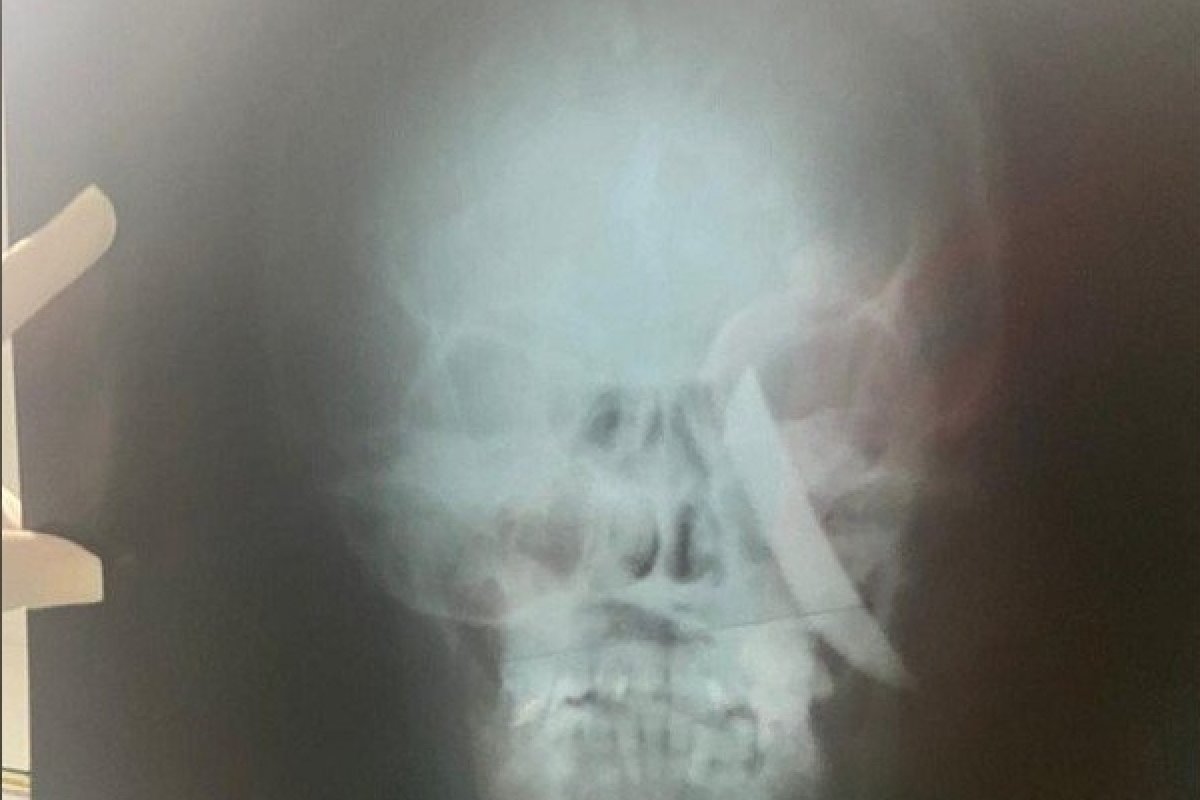

Mulher fica com uma faca cravada no crânio após tentativa de feminicidio

Após sofrer uma tentativa de feminicídio, uma mulher ficou com uma faca cravada no crânio nesta segunda-feira (8), em Morada Nova, no interior do Ceará. O suspeito de cometer o crime é o ex-companheiro da vítima, que foi preso em flagrante dentro de casa.